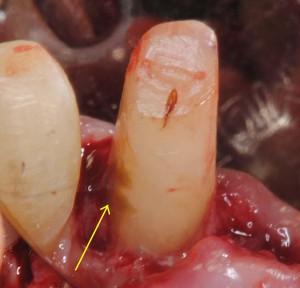

ブリッジの支えになる歯が歯周病なので歯周外科を行った。歯肉に隠れていた歯根表面に歯石が見える(矢印)。

歯石除去後ルーペで確認。取り残しがある(矢印)。肉眼治療の限界を感じる。できればマイクロスコープ使用が望ましい。

反対側の歯の歯石(矢印)。これをきちんととらないと、やがて歯がぐらぐらになってしまう。